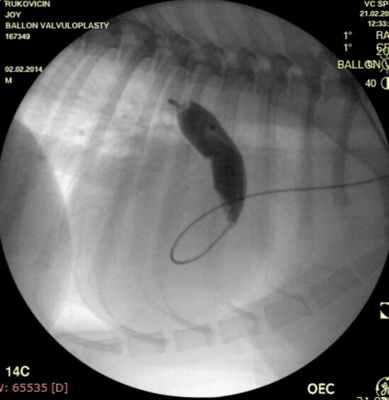

Проведено: баллонная вальвулопластика клапана легочной артерии (Тип А). Баллон Cordis maxi 40х20 мм. Инфляция до 5 атм. 10 попыток.

ЭхоКГ (после операции): ГД (градиент давления) на ЛА (легочной артерии) - 39 мм.рт.ст. РКЛА (регургитация клапана легочной артерии) – ср. - 16 мм рт.ст. Геометрия сердца не нарушена. Выраженное снижение градиента давления после баллонной дилатации КЛА (клапана легочной артерии) на 55%.